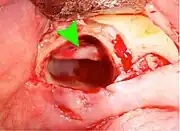

Wisdom teeth removal

Wisdom teeth removal (extraction) is the most common treatment for impacted wisdom teeth. In the US, 10 million wisdom teeth are removed annually.[20] The procedure can be either simple or surgical, depending on the depth of the impaction and angle of the tooth. Surgical removal is to create an incision in the mucosa of the mouth, remove bone of the mandible or maxilla adjacent the tooth, extract it or possibly section the tooth and extract it in pieces. This can be completed under local anaesthetic, sedation or general anaesthetic.[5] As of 2020, the evidence is insufficient to recommend one type of surgical practice over another.[21]

Coronectomy

Coronectomy is a procedure where the crown of the impacted wisdom tooth is removed, but the roots are intentionally left in place. It is indicated when there is no disease of the dental pulp or infection around the crown of the tooth, and there is a high risk of inferior alveolar nerve injury.[31]